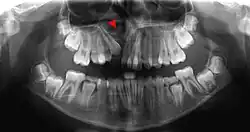

The density of the alveolar bone in a given area also determines the route that dental infection takes with abscess formation, as well as the efficacy of local infiltration during the use of local anesthesia. In addition, the differences in alveolar process density determine the easiest and most convenient areas of bony fracture to be used, if needed during tooth extraction of impacted teeth. During chronic periodontal disease that has affected the periodontium (periodontitis), localized bone tissue is also lost. The radiographic integrity of the lamina dura is important in detecting pathologic lesions. It appears uniformly radiopaque (or lighter).[24]